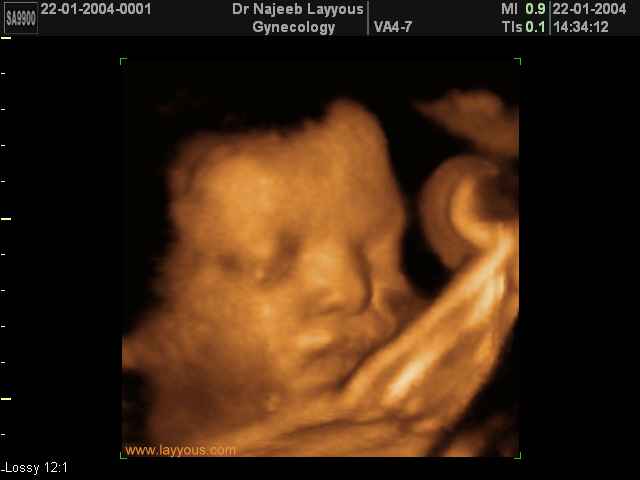

صور لوجه الجنين بجهاز الالتراساوند ثلاثي الأبعاد | الدكتور نجيب ليوس

صور لوجه الجنين بجهاز الموجات فوق صوتية ثلاثي الأبعاد